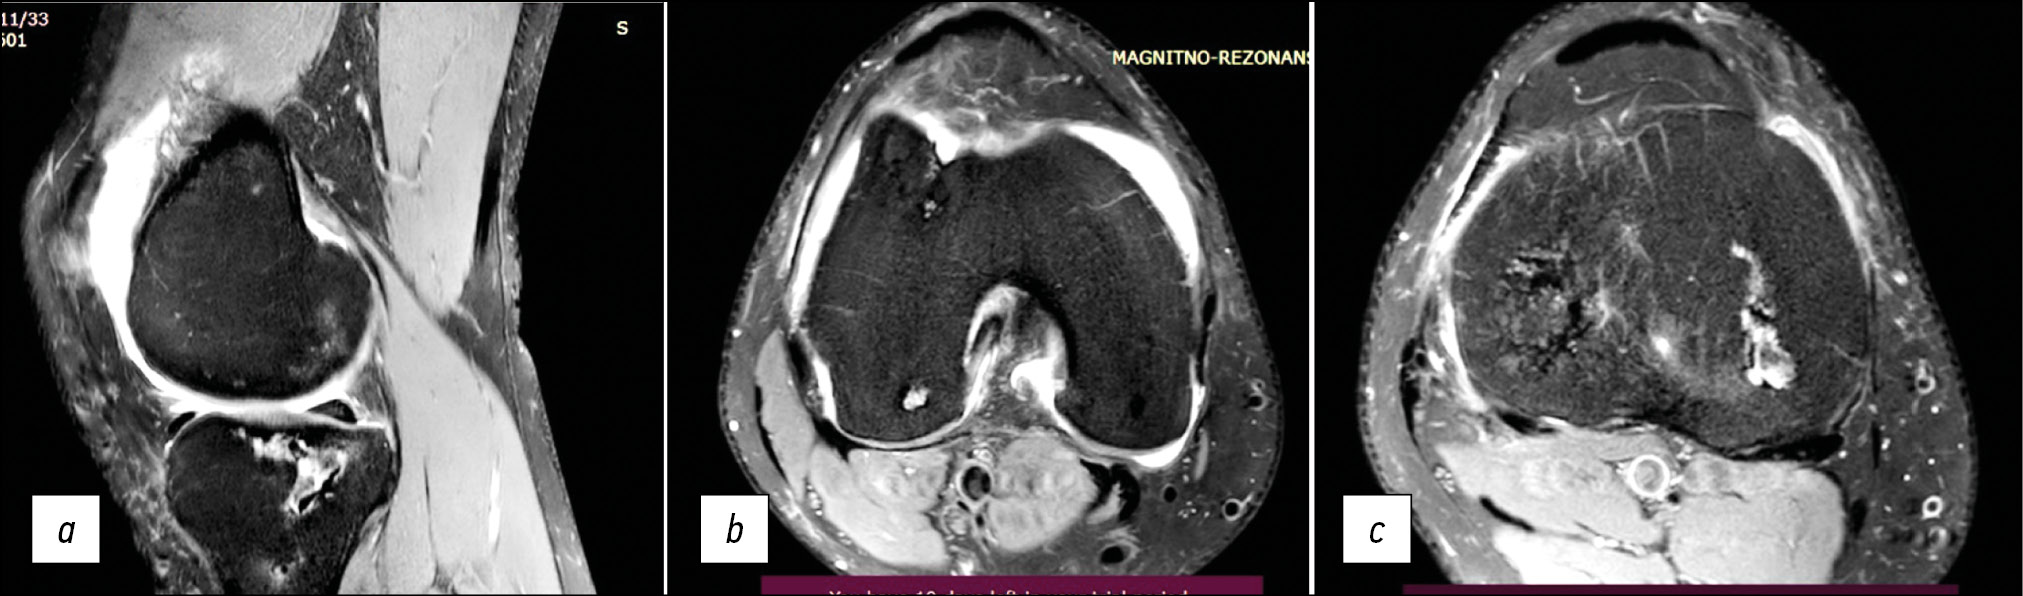

In polyneuropathies, including autoimmune neuropathies, nonspecific changes in the structure of peripheral nerves are also detected; an example is nerve thickening caused by thickening of nerve fibers in the composition of the nerve trunk, and a decrease in echogenicity. At the same time, differentiation into fibers and the clarity of the nerve contours are preserved (Fig. 8).

Fig. 8. Ultrasound examination of the tibial nerve in a patient with disimmune neuropathy illustrating nonspecific changes in the peripheral nerve structure. Transverse (a) and longitudinal (b) projections.

In COVID-19 patients, especially in the course of the disease, Parsonnage–Turner syndrome, which is an acute plexitis of the brachial plexus, can be diagnosed and has been found to be unilateral in 70% of cases [42–44].

Characteristic changes in the structure of the brachial plexus, which are visible on US imaging and are characteristic of Parsonage–Turner syndrome, include thickening and decreased echogenicity of the ventral branches of the C5, C6, and C7 spinal nerves, the primary superior, and middle plexus trunks in the supraclavicular part of the plexus (Fig. 9).

Fig. 9. Ultrasound examination of Parsonage–Turner syndrome. Thickening of the ventral branches of the C5, C6, and C7 spinal nerves and the primary upper and middle trunks of the plexus (arrows). Longitudinal (a) and transverse (b) projections of the supraclavicular part of the brachial plexus.